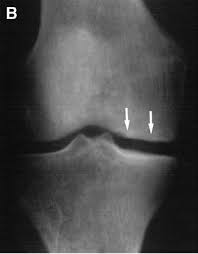

They are called the medial and the lateral femoral condyle, respectively. An imbalance of the muscles around the knee (some muscles are weaker than others.) overuse (repeated bending or twisting) of the knee joint, especially during sports. However, two of the patients had one or more fractures missed when they first presented. The medial femoral condyles are the bony protrusions on the inside edge of the bottom of the femur bone in each thigh. Osteochondritis dissecans (ocd) is an acquired, reversible, idiopathic lesion. Osteonecrosis of the medial femoral condyle presents as a sudden onset of pain on the medial side of the knee. This is associated with a positive bone scan and, frequently, a radiolucent lesion in the subchondral zone. Methods sixteen knees with a small medial femoral. The medial condyle is larger than the lateral (outer) condyle due to more weight bearing caused by the centre of mass being medial to the knee. Medial condyle of femur from wikipedia, the free encyclopedia the medial condyle is one of the two projections on the lower extremity of femur, the other being the lateral condyle. Root tear (radial tear) of the medial meniscus mild or moderate knee arthritis Osteonecrosis of the medial femoral condyle can be treated in a variety of ways depending on the stage of the disease. Of the six patients who had suffered an isolated fracture of their medial condyle, four of the patients had their fractures diagnosed on the first visit.

The radiographs demonstrated abnormal contour of the medial femoral condyle, consistent with an osteochondral defect, and a fabella posterior to the knee. Methods sixteen knees with a small medial femoral. It acts to support a significant amount of the patient's body weight. An imbalance of the muscles around the knee (some muscles are weaker than others.) overuse (repeated bending or twisting) of the knee joint, especially during sports. If there is a fracture (break) in part of the condyle, this is known as a fracture of the femoral condyle. The medial femoral condyle is supplied by a plexus of vessels from the descending genicular artery and the medial superior genicular artery. Damage may also be the result of a direct blow to the knee. Palpable to either side of the knee joint when it is bent, they are known specifically as the medial and lateral femoral condyles.

An articular cartilage injury, or chondral injury, may occur as a result of a pivot or twist on a bent knee, similar to the motion that can cause a meniscus tear. An imbalance of the muscles around the knee (some muscles are weaker than others.) overuse (repeated bending or twisting) of the knee joint, especially during sports. Juvenile ocd lesions have a better healing prognosis than adults. Osteonecrosis of the medial femoral condyle presents as a sudden onset of pain on the medial side of the knee. The radiographs demonstrated abnormal contour of the medial femoral condyle, consistent with an osteochondral defect, and a fabella posterior to the knee. Please see our knee injury protocol for additional information on this topic. Chondral injuries may accompany an injury to a ligament, such as the anterior cruciate ligament. Medial condyle of femur from wikipedia, the free encyclopedia the medial condyle is one of the two projections on the lower extremity of femur, the other being the lateral condyle. In the knee, chondromalacia is usually related to injury, overuse of the knee, and poorly aligned muscles and bones around the knee joint. The motions of the condyles include rocking, gliding and rotating. One presumed mechanism of injury is a stieda fracture (avulsion injury of the medial collateral ligament at the medial femoral condyle). Generally, ocd seems to affect males more commonly than females (between 2:1 and 3:1). According to the hospital for special surgery, the medial femoral condyle is the inside of the knee, and health issues dealing with it can be treated.

A bone fracture at this location is termed a femoral condyle fracture. Tendons and ligaments attach your kneecap to your shinbone and thigh. What is an articular cartilage defect and how is it treated? This is associated with a positive bone scan and, frequently, a radiolucent lesion in the subchondral zone. Damage may also be the result of a direct blow to the knee.